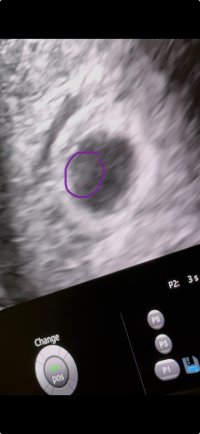

6+1 ble jeg satt tilbake fra 7+3 men med en bankene hjerte. Bildene ellers er veldig dårlige da. Legger ved et bilde fra filen. Der ser man det

Vedlegg

• IMG_0349.jpeg

IMG_0349.jpeg